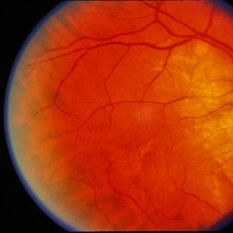

---thumb.jpg/image-square;max$300,300.ImageHandler) Age Related Macular Degeneration

Age Related Macular Degeneration

May 3 2013 by Suber S. Huang, MD, MBA, FASRS

Age related macular degeneration.

Condition/keywords: advanced geographic atrophy, atrophic scar, atrophic spot, geographic atrophy, macula lesion, pigment epithelial atrophy, red-free, window defect